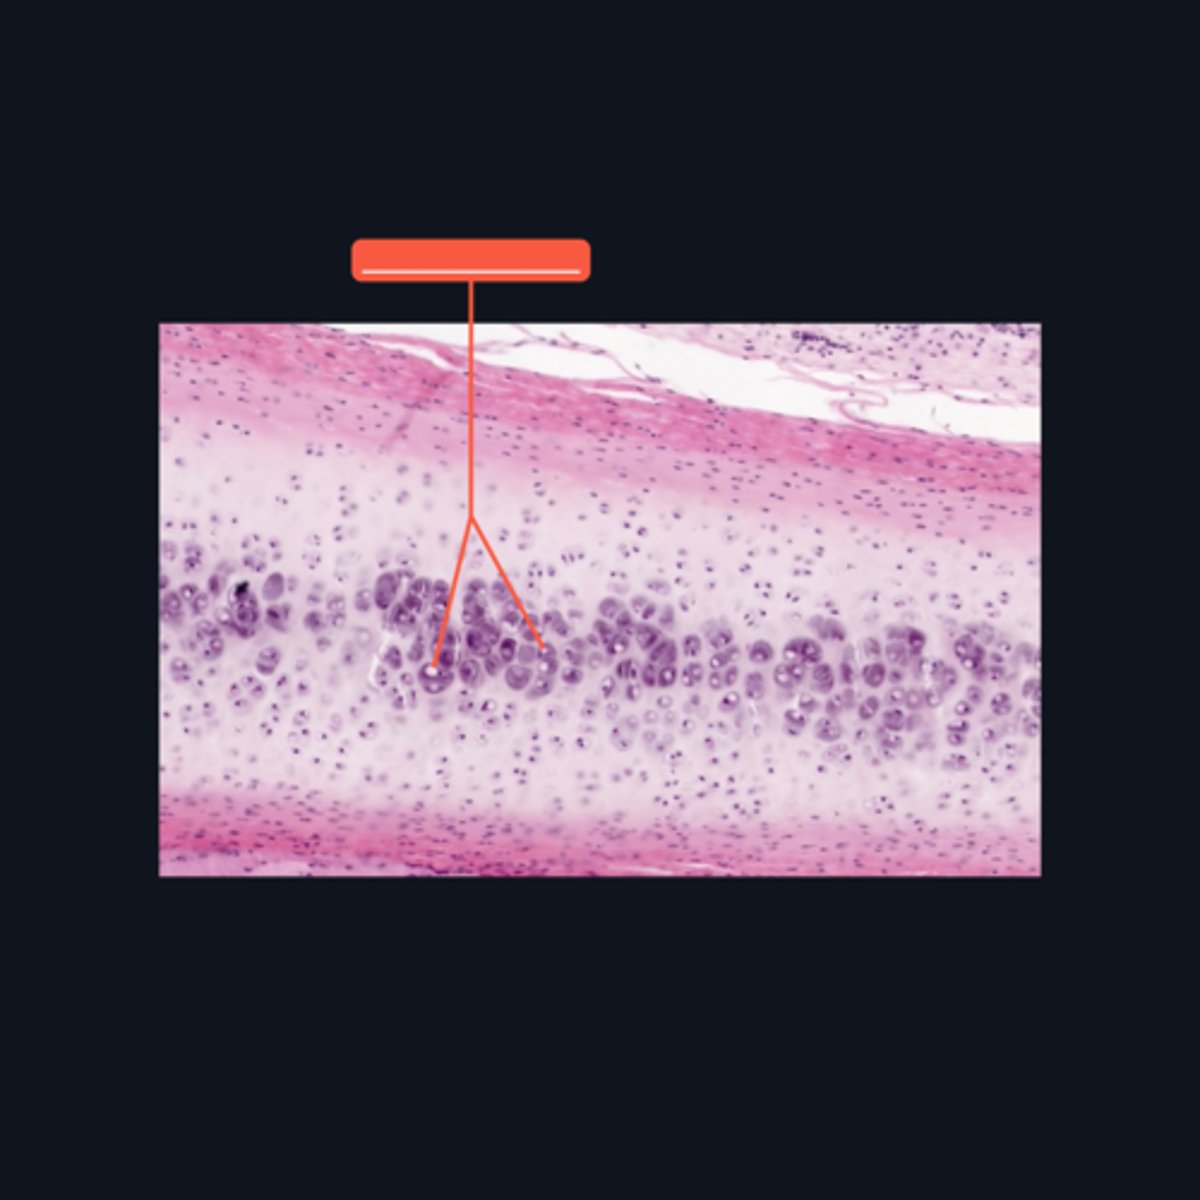

Hyaline cartilage

What structure is the presented? This is the most common type of cartilage in the body.

Type II Collagen

What type of extracellular fibers are present in hyaline cartilage?

Hyaline cartilage; joints, ends of sternal ribs, ligaments, tendons and respiratory tract.

In an adult body, ______ is found in the following locations (5) ___________.

Lacunae

In what structure can we locate a chondrocyte?

Cell nests

The chondrocytes in the central area of the cartilage form clusters, which are sometimes referred to as ________?

Chondronectin

In the ground substance of cartilage, what is the name of the fibronectin-like substance that promotes the adherence of collagen fibers to the cell surface of the chondrocyte?

Proteoglycans

Apart from water, the ground substance of hyaline cartilage is mostly made up of ____________.

Territorial Matrix; Glycosaminoglycans (GAG)

What do you call the intercellular substance that immediately surrounds the lacuna? This area is intensely basophilic because it is particularly rich in ___________.